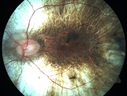

36 year old with vision loss for 14 years - Brother with choroideremia - Positive gene test. 20/80 OD and 20/160 OS

Choroideremia - Complete CHM gene deletion453 viewsVision loss since age 20 - now age 36 VA 20/160 (about) OU00000